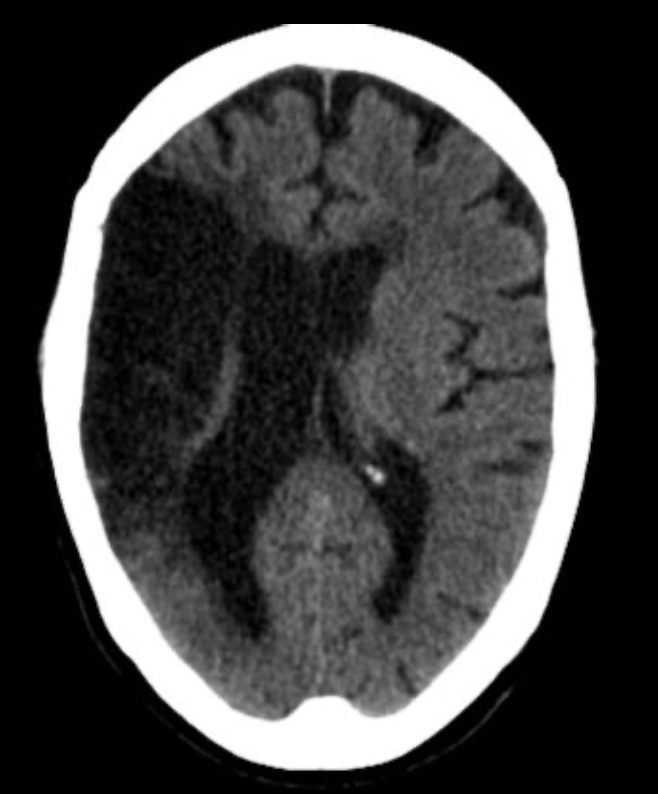

EVC isquémico

Fase cronica